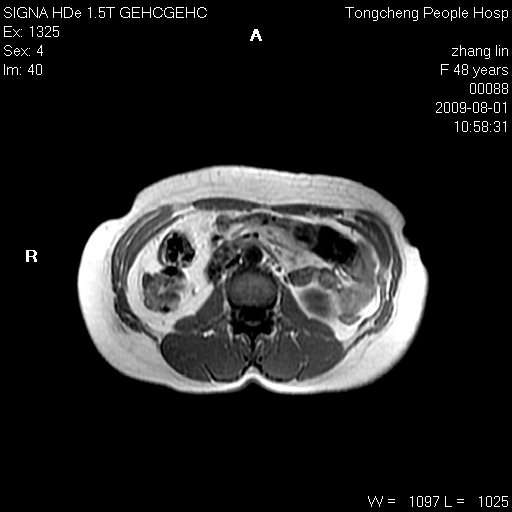

女,48岁。健康体检,彩超发现右肾占位性病变。平素健康。

临床诊断:右肾占位性病变,性质待定(囊肿?肿瘤?)。

上中腹部mr平扫+增强扫描,图像如下:

右肾上极见一类圆形病灶,t1wi呈等信号t2wi呈等高混杂信号,三期增强无强化,边界清---考虑囊肿出血。

同反相位均表现为等信号,病变无强化,考虑含蛋白的囊肿可能,弥散加权相或许有些帮助,

慢性胆囊炎